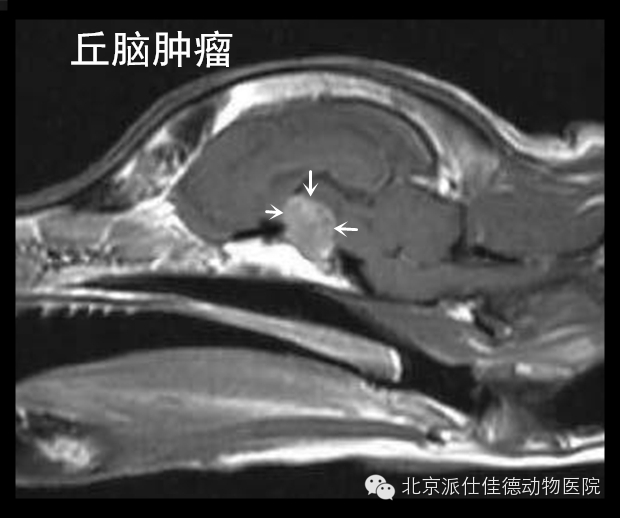

19.有些动物表现为全身脱毛、腹围增大,经诊断为肾上腺肿瘤或是下丘脑垂体出现肿瘤。